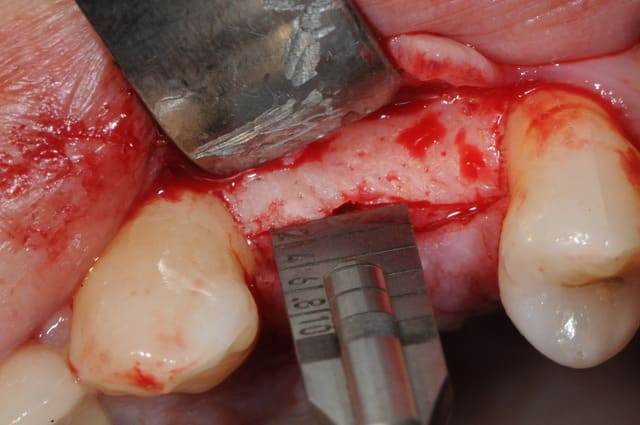

suite..

come ce con de patient fume et picole peut être aussi, il revient à 10 jours avec plusieurs fils de suture de perdu depuis au moins trois jours.

j'explique pourtant longuement aux patients que "si il y a un doute, c'est qu'il n'y a pas de doute"

comprenez, par là que si on pense avoir perdu un fil, j'incite les patients à venir IMMEDIATEMENT et sans RDV.

bref, cet imbé%$µ?"# se pointe et me dit que ça gène un peu.

tu parles! nécrose osseuse, exposition de l'implant et de la crête osseuse photo 1 et 2

donc pince gouge pour l'os "mort" cruantage de berges gingivales, irrigation, sutures bref, je fais le pompier de service.

photo 3: contrôle à 4 jours, le plus grave est passé!

n’empêche que les dégâts sont considérables...la tête de l'implant est exposée.